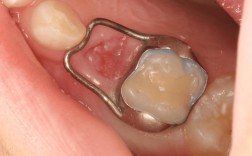

在正畸治疗中,支抗控制是核心难点,尤其当需要前牙内收或后牙移动时,大牙常作为“支抗牙”为其他牙齿移动提供支撑,绞钢丝通过将托槽与带环或托槽紧密结扎,将大牙与整个矫治系统“锁定”,避免其在受力时发生非预期移动,在拔牙矫正中,若需将前牙向内收,绞钢丝会将上颌磨牙结扎在颊面管上,通过弓丝传递的力量,确保磨牙仅发生微小的近中倾斜,而非整体前移,从而为前牙移动提供充足支抗。